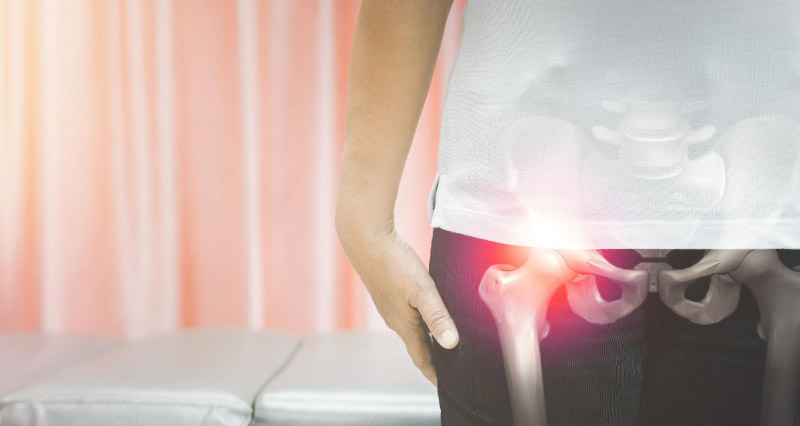

Đau khớp háng bên phải là tình trạng phổ biến ảnh hưởng trực tiếp đến khả năng vận động và sinh hoạt hàng ngày. Đây là khu vực nối liền giữa xương chậu và xương đùi, đóng vai trò quan trọng trong việc chịu lực và hỗ trợ chuyển động của cơ thể. Khi khớp háng bị tổn thương, người bệnh có thể gặp khó khăn trong việc đi lại, đứng lên hoặc giữ thăng bằng. Trong bài viết dưới đây, ECO Pharma sẽ cùng bạn tìm hiểu các nguyên nhân và biểu hiện của tình trạng đau khớp háng bên phải, từ đó giúp phát hiện sớm và có hướng điều trị hiệu quả.

Khớp háng có hình chỏm cầu, là điểm kết nối giữa xương đùi và xương chậu. Đây cũng là một trong những khớp lớn nhất của con người. Chức năng của bộ phận này dùng để di chuyển, nâng đỡ trọng lượng cơ thể và giữ thăng bằng. Cụ thể các chức năng của khớp háng bao gồm: hỗ trợ các chuyển động như đi lại, chạy nhảy; hấp thụ lực và phân phối lực đối với cơ thể; là trụ đỡ cho phần thân trên, duy trì sự thăng bằng; là trung tâm của của các chuyển động phức tạp như gập, duỗi,…

Đau khớp háng bên phải là cảm giác đau nhức, khó chịu tại khớp háng bên phải hoặc các vùng xung quanh khớp. Cơn đau khớp háng có thể diễn ra tạm thời, kéo dài hoặc không liên tục. Chẳng hạn như: chỉ đau khi di chuyển và sẽ thuyên giảm khi nghỉ ngơi; đau nghiêm trọng hơn vào buổi sáng sớm; đau vào ban đêm, nhất là khi nằm ngủ nghiêng về phía háng bị đau.